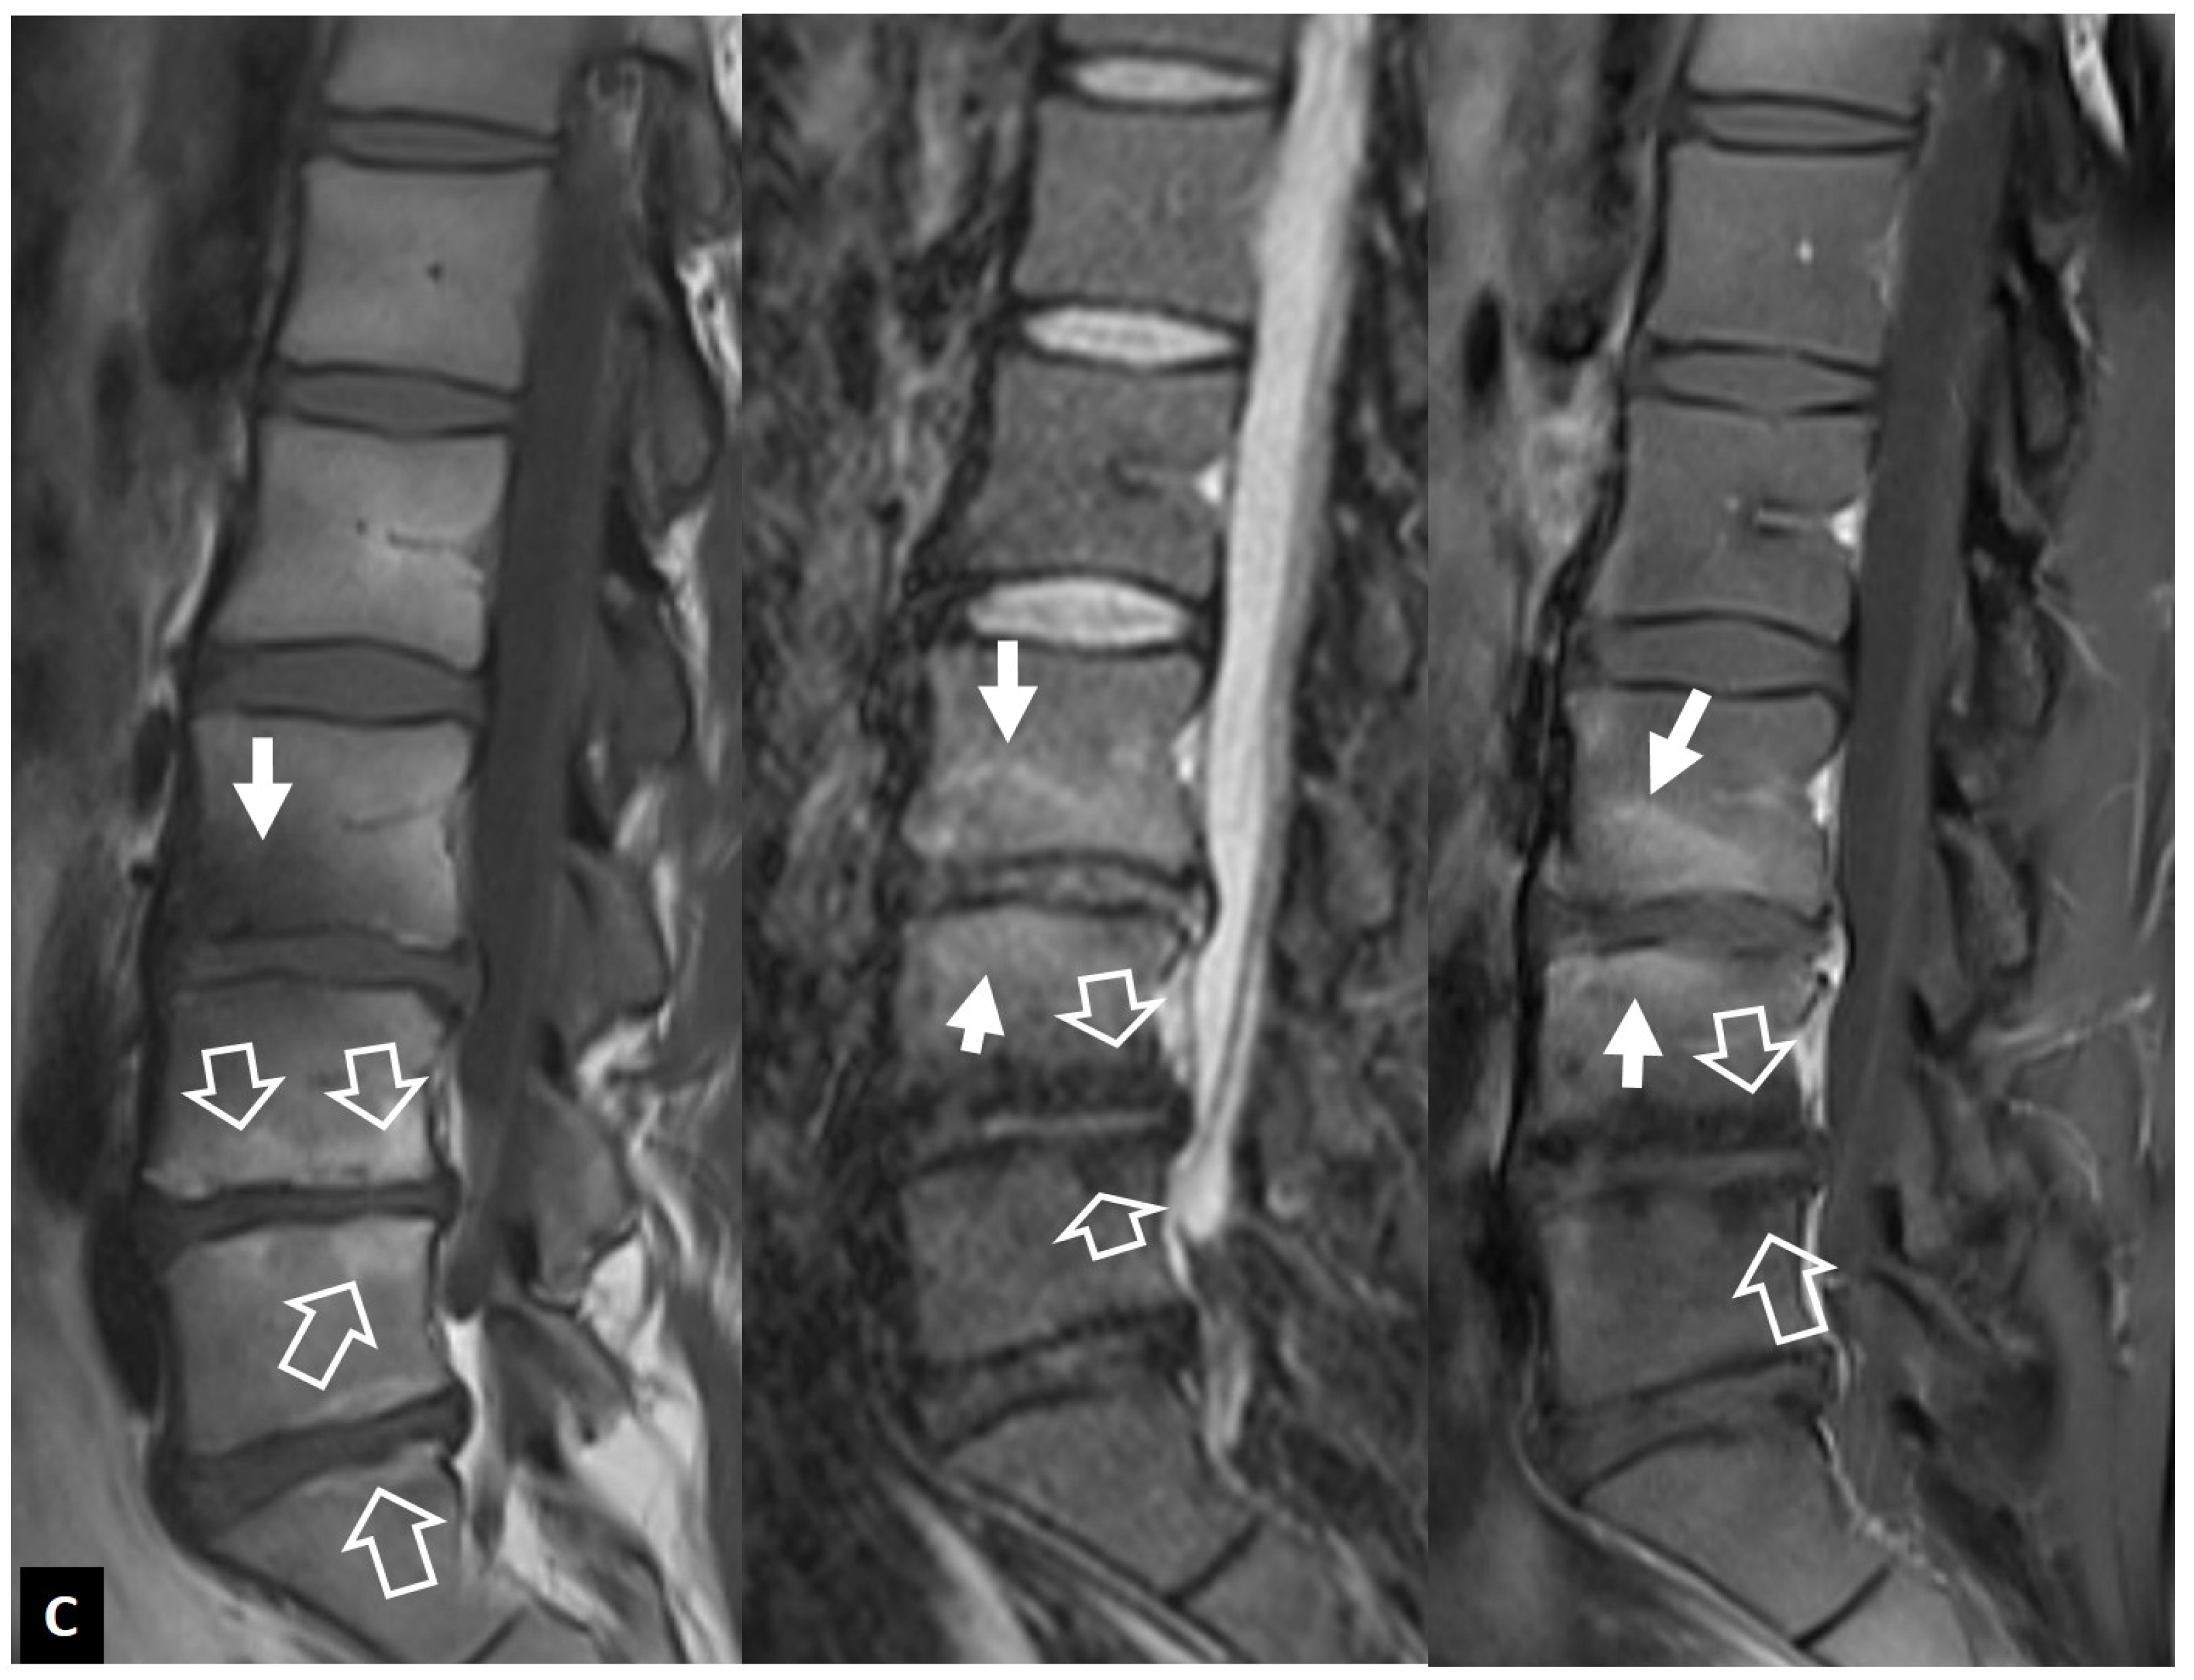

2.1.2. Aseptic Spondylodiscitis

2.1.3. SAPHO Syndrome

2.1.4. Destructive Spondyloarthropathy

2.1.5. Crystal Deposition

2.1.6. Post-Operative Aseptic Discitis

2.1.7. Trauma